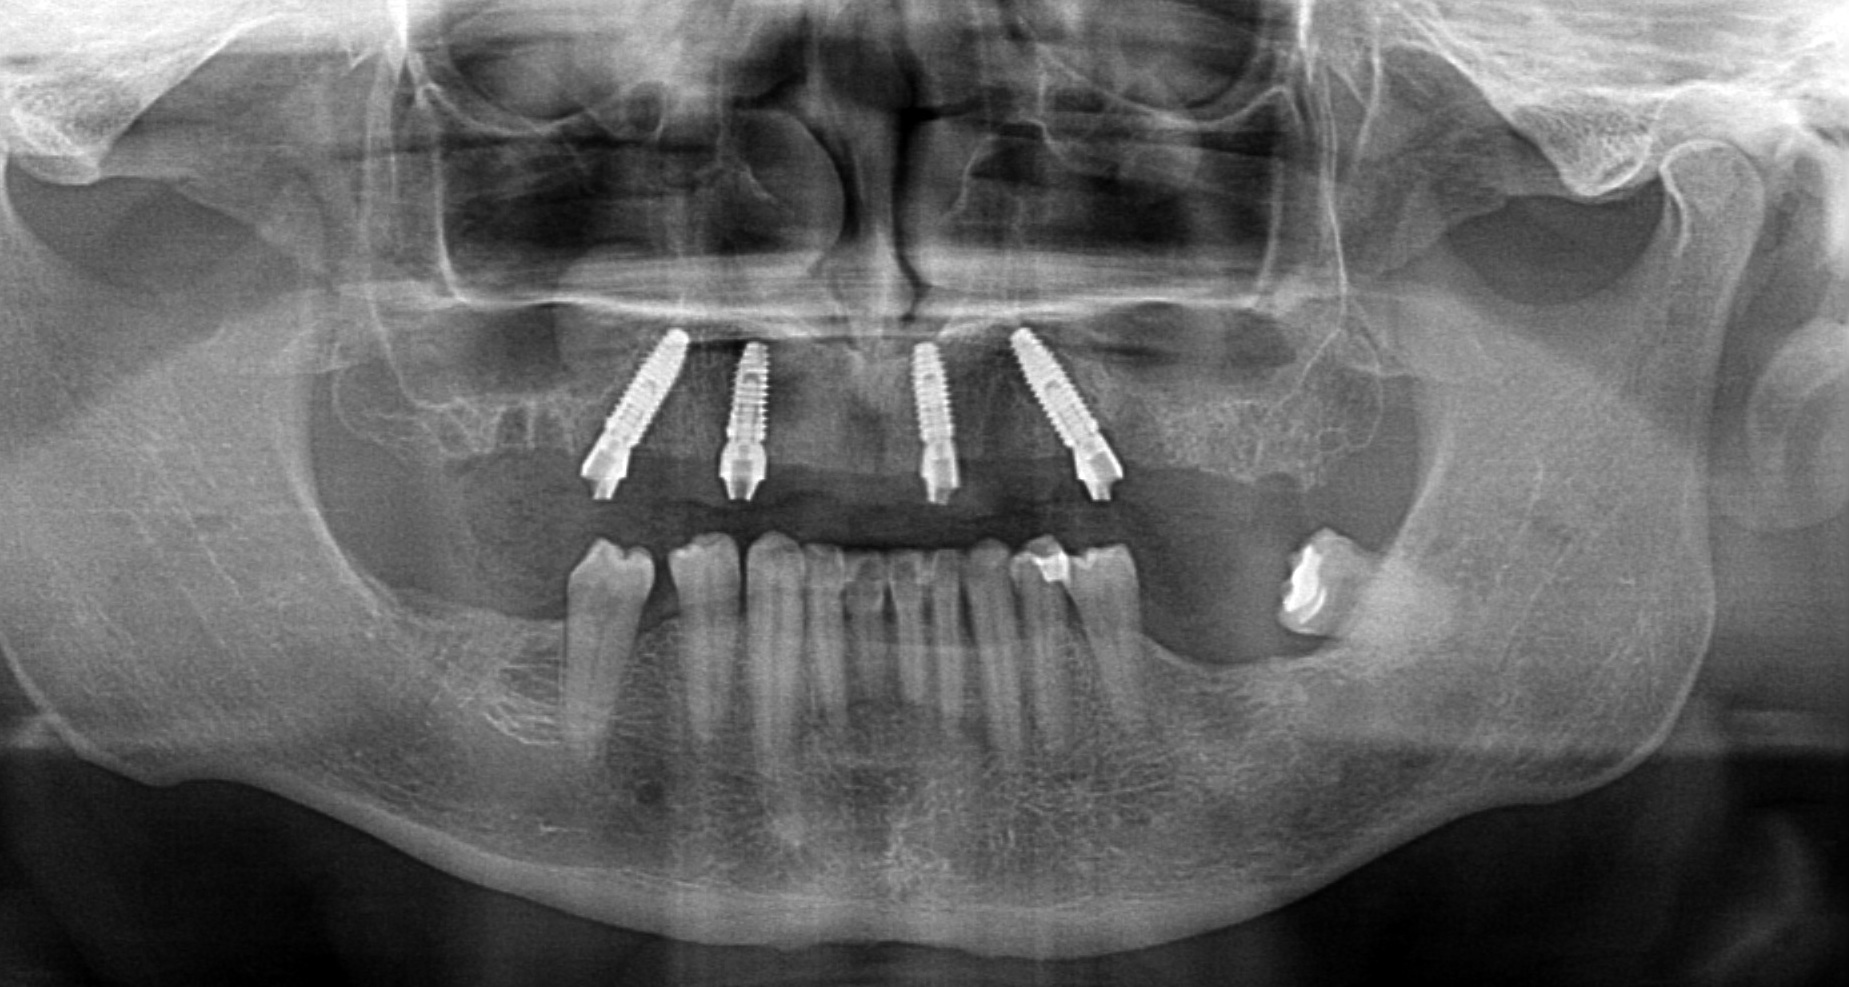

2. Protezy na belce retencyjnej – stabilność i komfort jedzenia

Protezy wsparte na belce to rozwiązanie łączące zalety implantów ze względną prostotą użytkowania. Belka retencyjna to metalowa (najczęściej tytanowa) konstrukcja przykręcona do 4-6 implantów, na której mocowana jest proteza.

Implanty zostają wszczepionych w szczękę lub żuchwę, a następnie połączone belką metalową. Proteza posiada specjalne zatrzaski lub klipsy, które mocują ją na belce – zapewniając wyjątkową stabilność, ale jednocześnie możliwość wyjęcia do higieny.

Przypadek 2